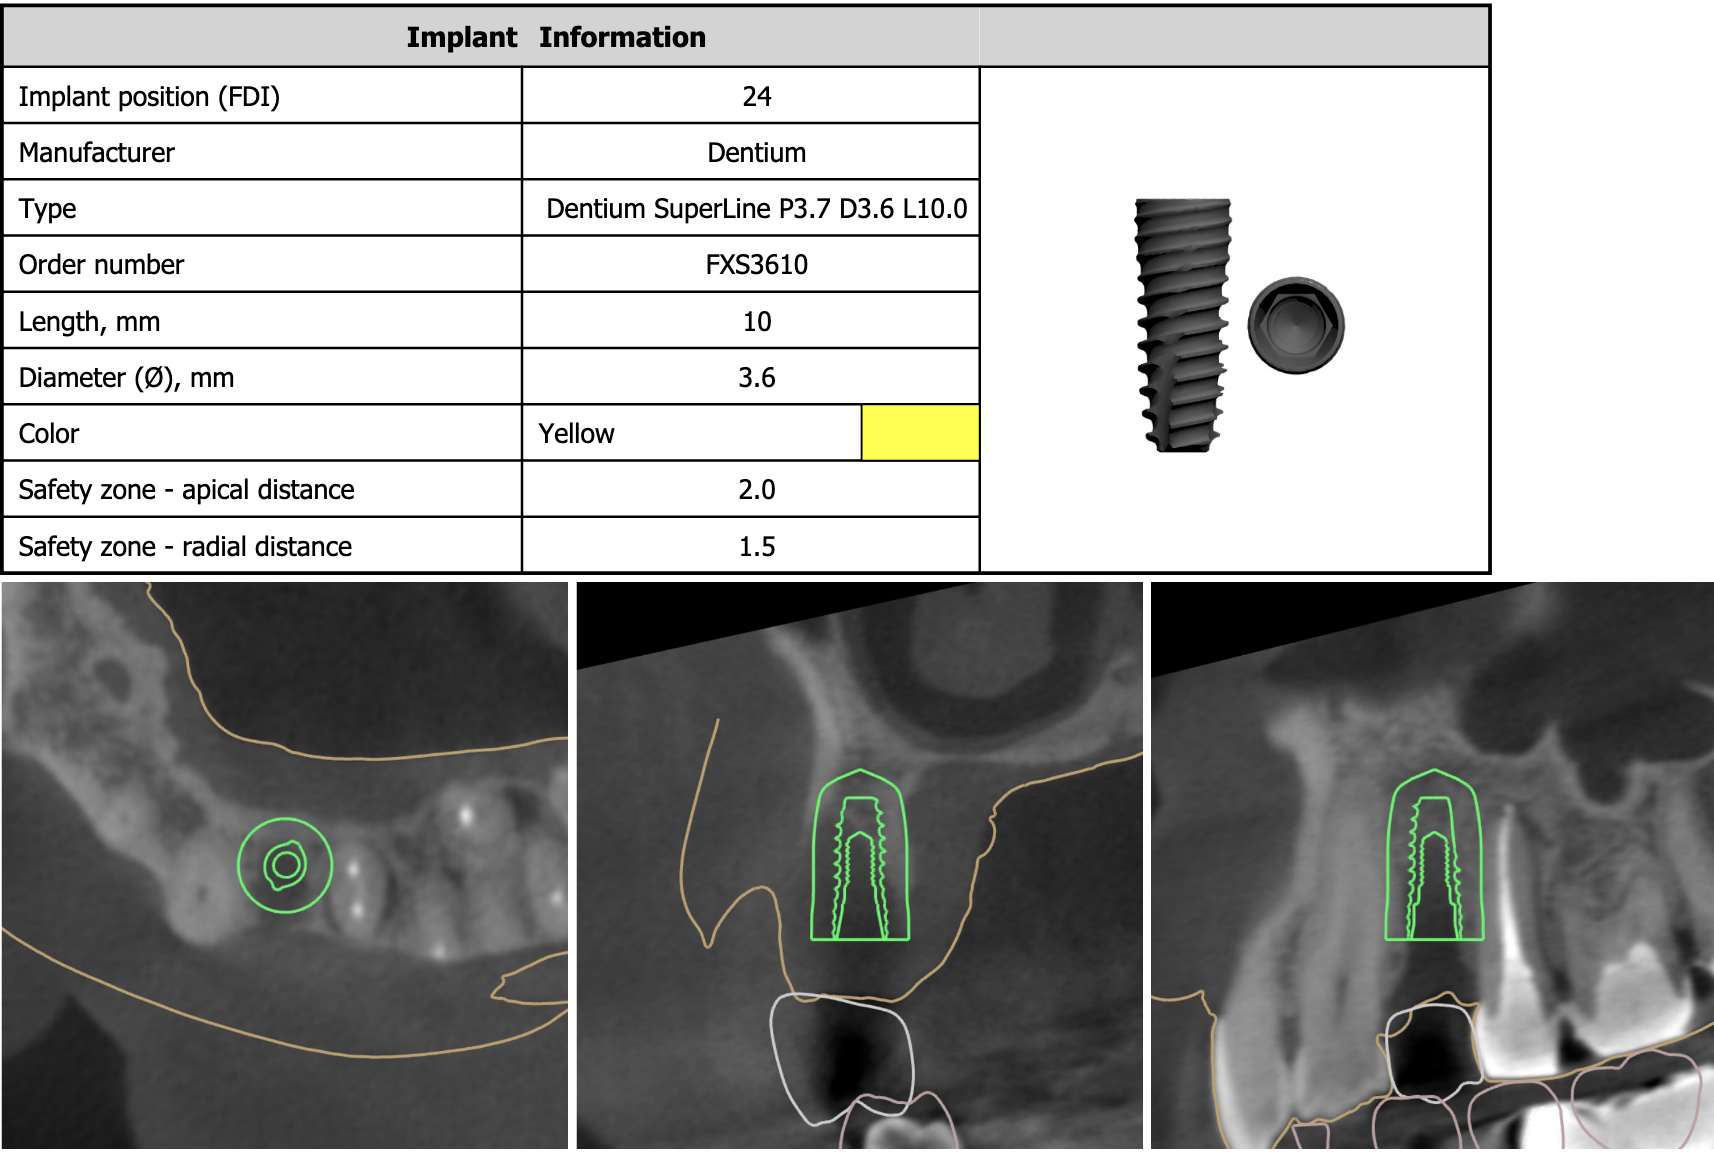

全顎的に複数の治療部位で、インプラント・ブリッジ・ダイレクトボンディング・セラミッククラウンなど、適切な治療方法を組み合わせて包括的な治療を進めました。

この「T-scan」はインプラント治療にも応用できる点が他の計測装置との違いの一つです。「I-24」と表示されているのはインプラントが埋入されている表記で、そこに他の歯と同じ力が掛かっている事を示しています。これは通常のリボン紙(咬合紙)では全くわかりません。このように天然歯、補綴歯、インプラント治療歯の力の違いを把握すれば、インプラントに掛かる力による治療後のトラブルを回避出来ると考えます。